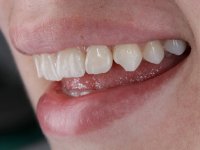

Female patient, 24 years of age, non-smoker. The clinical situation resulted from an orthodontic treatment performed with the intention of resolving a problem of unilateral agenesis of the left lateral incisor. After orthodontic correction, an implant was placed at the site of tooth 2.2. During the period of osseointegration the patient used a removable orthodontic appliance with a prosthetic tooth. Upon assessment of the situation, I registered the following aesthetic conditions:

1. The cervical level of the teeth 1.3.1.2 and 1.1 are at a more incisal level than the teeth 2.1 and 2.3.

2. The distal papillae of 2.1 and mesial of 2.3 disappeared.

3. Slight radicular exposure in distal 2.1 and mesial 2.3.

4. The edentulous space corresponding to the high and narrow 2.2.

5. Tooth 1.2 with microdontia and rolled.